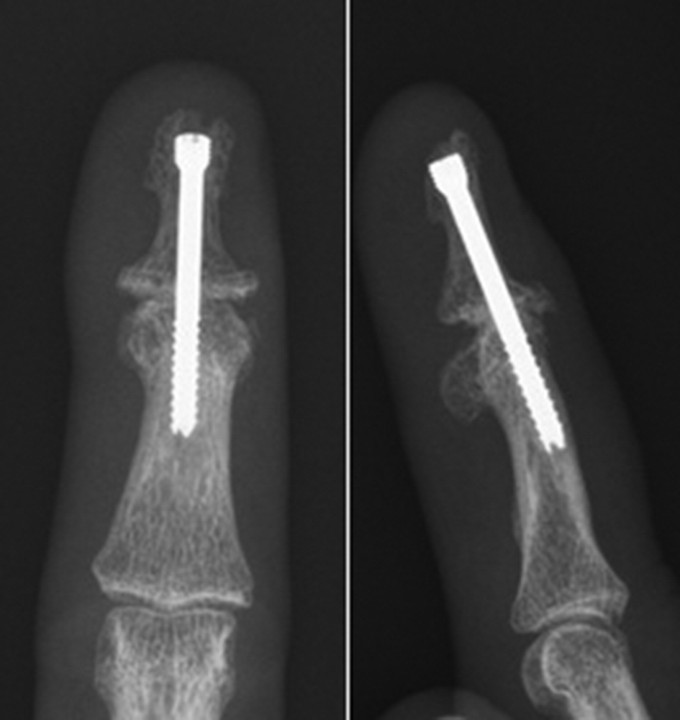

The DIP joint is biomechanically forgiving. For most people, fusing this joint straight or with a small bend does not noticeably affect function – you can still make a fist, grip tools, and type. So if a DIP joint becomes a small, concentrated source of pain from RA or secondary osteoarthritis, fusion (arthrodesis) is often an excellent, durable solution. The trade-off is simple: no motion, no pain.

Figure 5. X-ray showing fusion of the terminal finger joint (DIP joint) using a compression screw.